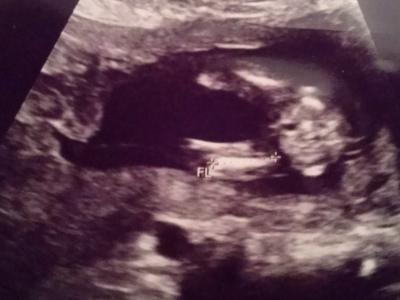

Hi, Was meint ihr? Liebe Grüße

Meine FA war sich erst nicht sicher, meinte aber dann doch ganz sicher Mädchen. Bin jetzt trotzdem verunsichert. Liebe Grüße

Ich tippe auf Mädchen. Bei meinen Töchtern sah das auch so aus. Bei meinem Sohn sah das GANZ anders aus.

Ich hätte jetzt eher auf Junge getippt... Sollen bei Mädchen nicht immer 3 Striche zu sehen sein?